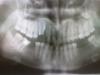

K-boy Опубликовано 10 августа, 2011 Автор Поделиться Опубликовано 10 августа, 2011 Bier Спасибо за ответ. Я решил капитально заниматься со своими зубами, и даже готов восемь месяцев носить брикет. Насчет 13 и 14 зубов сегодня стоматологом еще раз поговорили и решили удалить. А вместо них поставит временно зуб, прикрепленный к пластинку. Ну теперь план такой: удалить 13 и 14 зубов, одеть брикет и пластинку. По происшествии какое то времени ставить имплантаты. Но вопросы есть. 1. В моем случае кости позволяет ставит имплантат или нет? 2. Можно ли как то определит вероятность что имплантаты приживутся в моем организме? Все таки это долго и дорого. 3. Предлагают разные имплантаты и производство разных стран. Как их выбирать? 4. Правильно ли мы выбрали план лечения?5. Что если ставить имплантаты без ношения брикетов? Качество сильно ухудшиться?6. И последнее как Вы планировали б если я был вашим пациентом?Прошу прошения, вопросов много. Но с другой стороны не хочу и в этот раз ошибиться, тратить свое время и деньги впустую. Спасибо. Ссылка на комментарий

Bier Опубликовано 11 августа, 2011 Поделиться Опубликовано 11 августа, 2011 1. по плоскому снимку можно ответить лишь на 66,6% третьего измерения мы не видим. на 66,6 - хватает.2. Вероятность в среднем 96-98%3. Опираться на выбор врача.4. Да, план верный в целом.5. Качество чего? имплантатов - нет, а вот итоговый результат - думаю сильно.6. У вас верный план. Ссылка на комментарий